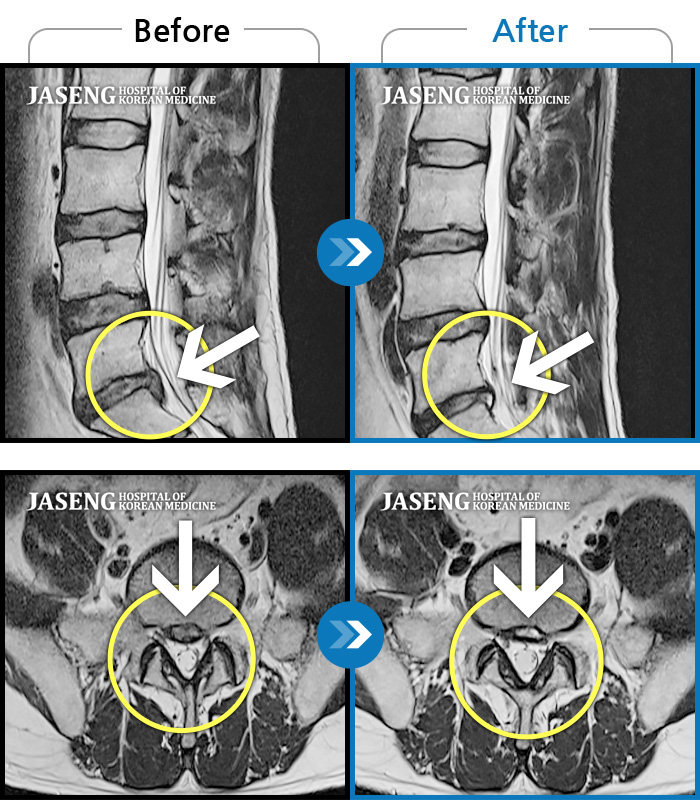

MRI 치료사례

허리통증과 다리저림